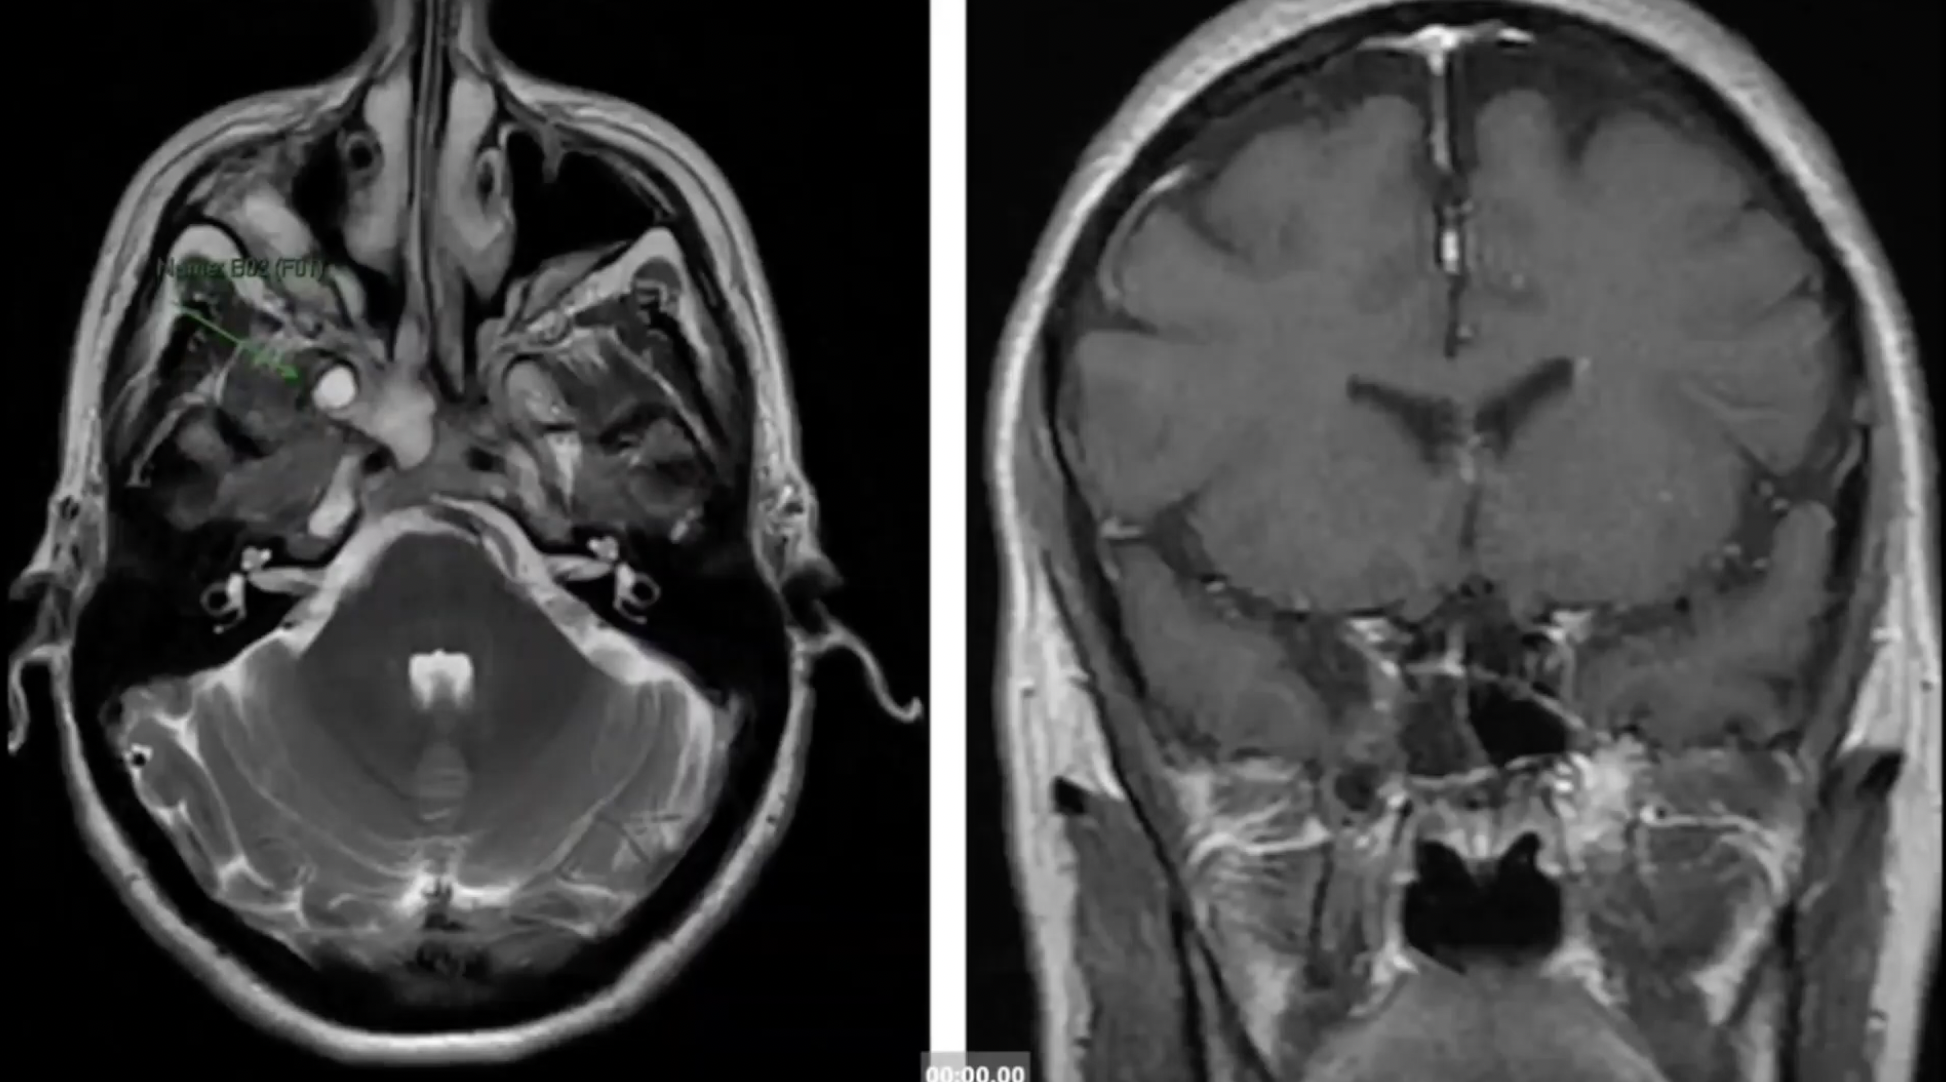

A purely endoscopic endonasal approach was used to remove suprasellar lesions in a series of 10 patients. Five lesions were prechiasmal (three tuberculum sellae and two planum sphenoidale meningiomas) and five were post-chiasmal (four craniopharyngiomas and one Rathke cleft cyst). The floor of the planum sphenoidale and the sella turcica was reconstructed using a multilayer closure with autologous and synthetic materials. Spinal drainage was performed in only five cases. Complete resection of the lesions was achieved in all but one patient. The pituitary stalk was preserved in all but one patient, whose stalk was invaded by a craniopharyngioma and who had preoperative diabetes insipidus (DI). Vision improved postoperatively in all patients with preoperative impairment. Six patients had temporary DI; in five, the DI became permanent. Four patients with craniopharyngiomas required cortisone and thyroid replacement. After a mean follow up of 10 months, there was only one transient CSF leak when a lumbar drain was clamped prematurely on postoperative Day 5.